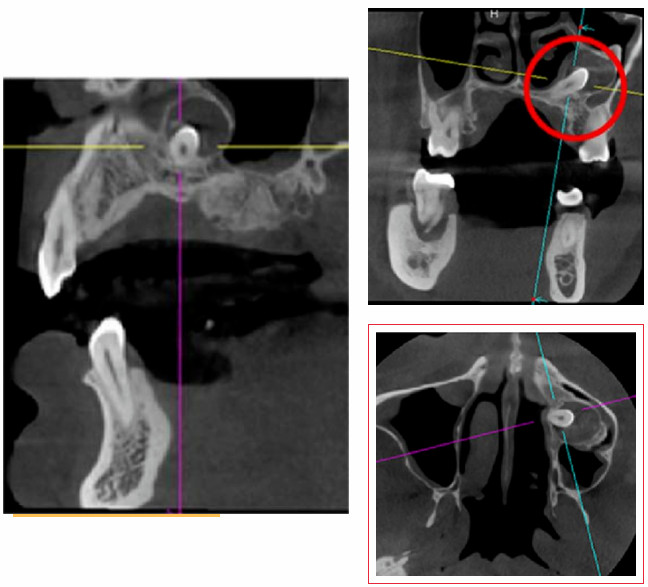

门诊采用CBCT三维影像技术,精准定位埋伏牙位置、形态及与周围神经关系。根据患者口腔条件、埋伏牙位置及风险因素,定制个性化精准拔牙方案,减少不必要的创伤与风险。